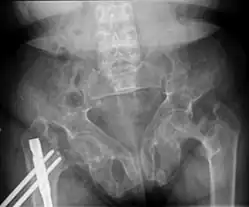

Brown tumors in the pelvis and a hip fracture.[18] -

Renal osteodystrophy is usually diagnosed after treatment for end-stage kidney disease begins; however the CKD-MBD starts early in the course of CKD.[1][6] In advanced stages, blood tests will indicate decreased calcium and calcitriol (vitamin D) and increased phosphate, and parathyroid hormone levels. In earlier stages, serum calcium, phosphate levels are normal at the expense of high parathyroid hormone and fibroblast growth factor-23 levels. X-rays will also show bone features of renal osteodystrophy (subperiostic bone resorption, chondrocalcinosis at the knees and pubic symphysis, osteopenia and bone fractures) but may be difficult to differentiate from other conditions. Since the diagnosis of these bone abnormalities cannot be obtained correctly by clinical, biochemical, and imaging methods (including measurement of bone-mineral density), bone biopsy has been, and still remains, the gold standard analysis for assessing the exact type of renal osteodystrophy.[6][16]